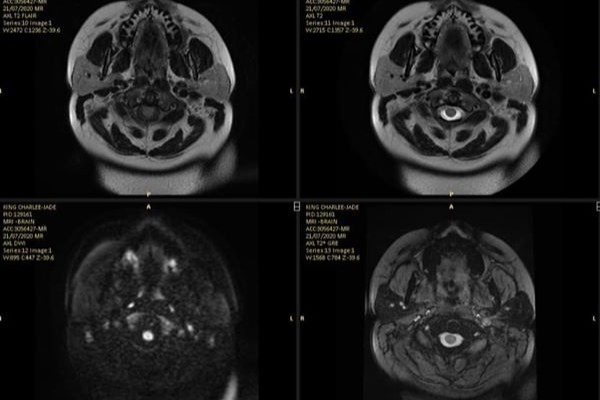

Although all that has come to a crashing halt. For Charlee-Jade’s life as well as the lives of everyone that cares about her changed forever with just one fateful phone call in July. An hour after having an MRI, Charlee-Jade received a call where she was instructed to go to her nearest emergency room immediately as a brain mass had been discovered.